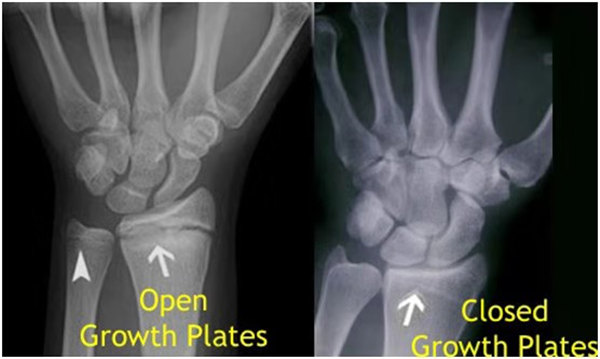

其實想要了解孩子的生長發(fā)育情況或者說孩子未來身高的趨勢,測骨齡是個好辦法。臨床上通常拍攝兒童的左手正位X光片 , 采用《中華-05》骨齡標(biāo)準(zhǔn)對手腕骨發(fā)育程度進行骨齡評價。

我們都知道,人體的高矮是由骨骼的生長發(fā)育決定的,特別是下肢長骨。長骨呈長管狀,在長骨的兩端有一種專管骨骼生長的骺軟骨,它與干骺端之間有一盤狀軟骨結(jié)構(gòu)稱為骺板(線),在幼兒的X光片上表現(xiàn)為一條較寬的透光帶。 (見下圖)